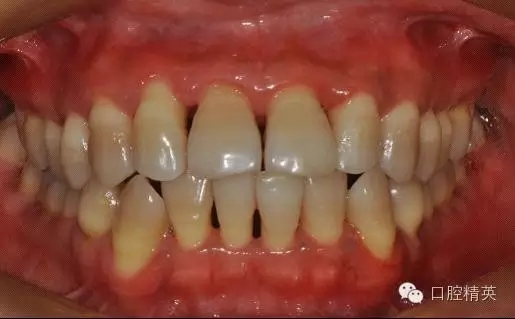

本病例 :女 34歲,主訴刷牙出血,覺(jué)牙齒輕度松動(dòng)一年。

檢查見(jiàn)大量齦上及齦下結(jié)石,探診出血,牙周袋較深,32-42 II度松動(dòng)。X線片顯示牙槽骨水平吸收。

診斷:成人慢性廣泛性中度牙周炎。

治療前: